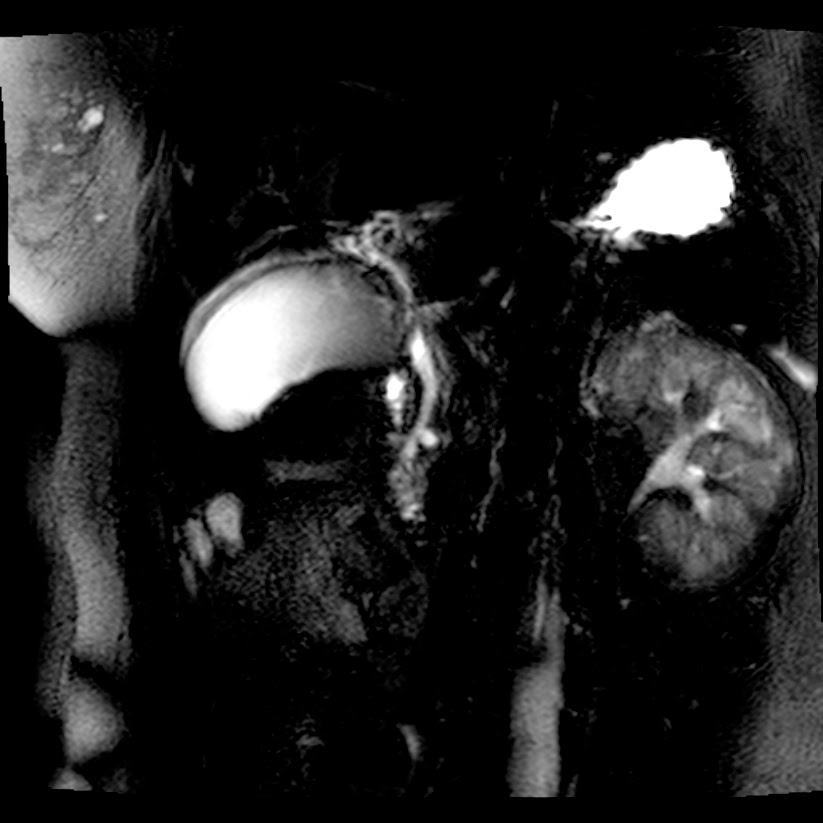

Caso interesante #5

Paciente con dolor en hipocondrio derecho.